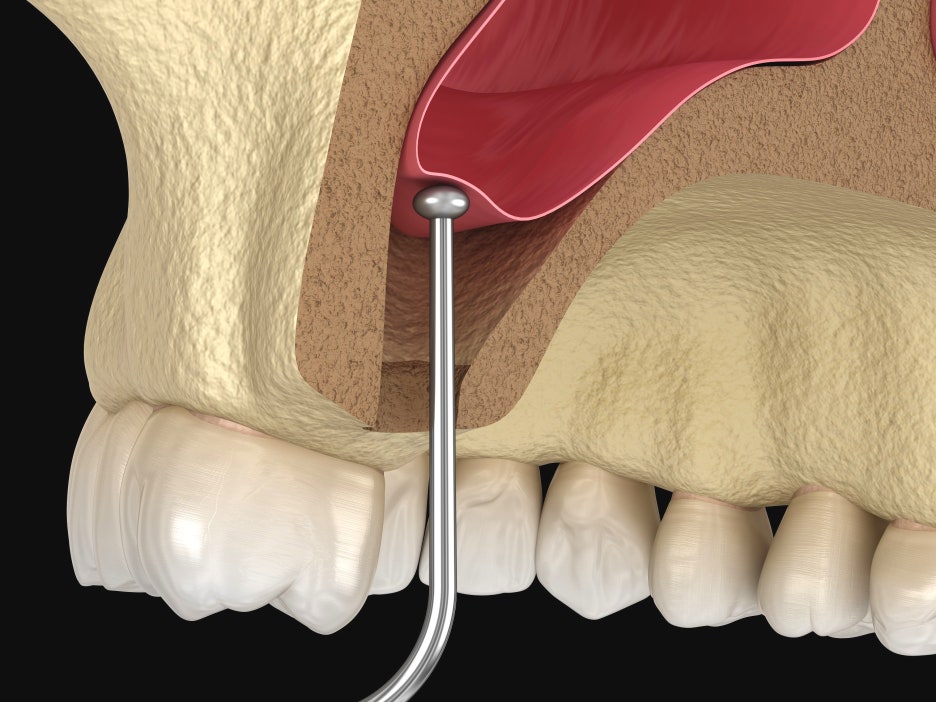

상악동거상술은 계란껍질을 까면 안쪽에 있는 얇은 막과 유사한 상악동막을 들어올리는 수술을 의미합니다.

임플란트를 식립하려고 하는 위치에 드릴로 구멍을 뚫어 수직으로 접근해 상악동막을 들어올리고 뼈이식을 진행하는 것입니다.

말 그대로 옆에서 접근해 뼈를 뚫고 상악동막을 들어올려 골이식재를 채워넣는 것입니다.